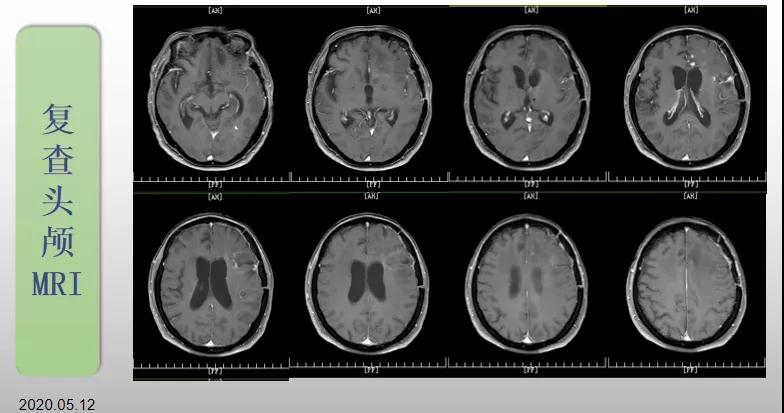

70歲的郝女士去年曾在外院查出“左額島葉”膠質母細胞瘤(WHO Ⅳ級),并做了左側額島葉占位性病變切除術。術后進行了同步放化療。由于治療條件有限,郝女士慕名來到我院就診。賀世明主任率領醫護團隊立即為郝女士進行了全面的檢查,決定為其進行綜合治療 電場治療。經過三個多月的綜合治療,患者復查頭顱MRI病變較前明顯縮小。出院時,郝女士神志清醒,睡眠飲食正常,說話很流利。“我是躺著進來的,現在不用人攙扶,自己就可以走出病房了。”郝女士拉著醫護人員的手說。